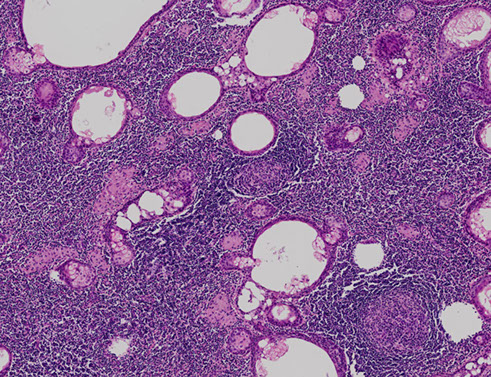

Papillary Cystadenoma Lymphomatosum (Warthin tumor)

2nd MC salivary gland tumor (~10% overall salivary gland tumors)

- MC in male smokers over 50 yo, bilateral (in 1/20?)

- arises from lymph tissue w/in parotid gland and is usually multifocal

Gross: filled c grumous material (from cysts)

Micro: Double layer composed of outer columnar cells and inner cuboidal cells lining reactive (not neoplastic) lymphoid tissue [comes from native lymph tissue of parotid]

- outer layer filled with mitochondria and appears reddish (termed "oncocytic"); the outer epithelial layers are the neoplastic component of Warthin's

- may infarct if becomes too big and have central necrosis

- deprive oncocytes of O2 a little bit and they will infarct, so watch out for reactive changes

- can have "motor oil" background cytologically

***WAR THE NODE (lymph node, that is)***

- WarthiN looks like a lymph Node

Tx: Superficial parotidectomy

- may infarct if untx'd

Px: may rarely transform into a higher-grade tumor